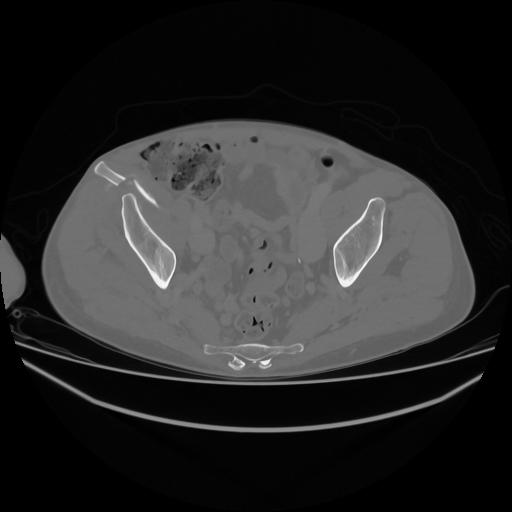

5 CUERPO,CE,Vol,1.0,CUERPO,,